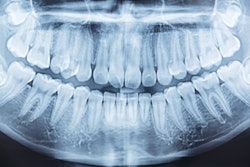

Some of the most pivotal moments in the patient experience occur when patients are in the exam chair. As dental professionals, we're used to seeing disease indications on x-rays and can quickly spot what may need a closer look. It's what we do every day. But for a patient, it can be tough to understand what's happening inside their mouth when we’re pointing at various shades of gray on digital film. My practice, Arch Dental of Manhattan, began using dental AI to explore its capabilities as a diagnostic aid and tool for patient communication, and we’ve been impressed so far.

Patients who can easily comprehend the issues affecting their oral health feel more involved in their treatment decisions. The ability to visually depict areas of concern on x-rays more clearly cannot be understated. This helps patients see for themselves the issues that need to be addressed and, with your guidance, better understand treatment recommendations.

AI can also be instrumental in helping patients better understand the outcomes of their treatments. By creating before-and-after image results with a dental AI overlay, you can easily walk patients through positive changes that stem from following treatment recommendations -- and on the other side of the coin -- the adverse effects of delaying treatment. In either case, this can be particularly effective for patients who are hesitant about specific types of treatments or who have previously had negative dental care experiences.